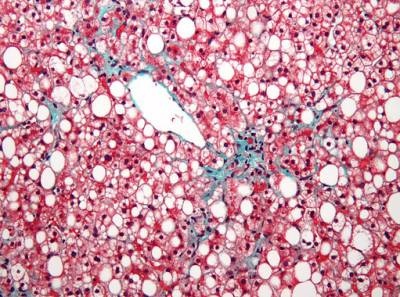

Fotografía microscópica mostrando un hígado graso. (Foto: Wikipedia)

Esta patología incluye un amplio abanico de alteraciones hepáticas que van desde una acumulación excesiva de triglicéridos en el hígado (esteatosis hepática) hasta la esteatohepatitis no alcohólica.

Utilizando diferentes modelos celulares y animales, los autores demuestran que la deficiencia PPARb/d y de FGF21 favorecen el aumento de los niveles de VLDLR y el consiguiente desarrollo de esteatosis hepática.